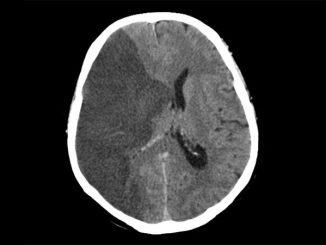

Tenecteplase Noninferior to Alteplase for Ischemic Stroke: TRACE-2

Tenecteplase is as effective as alteplase with respect to disability outcomes and safety in Chinese patients with ischemic stroke, a […]